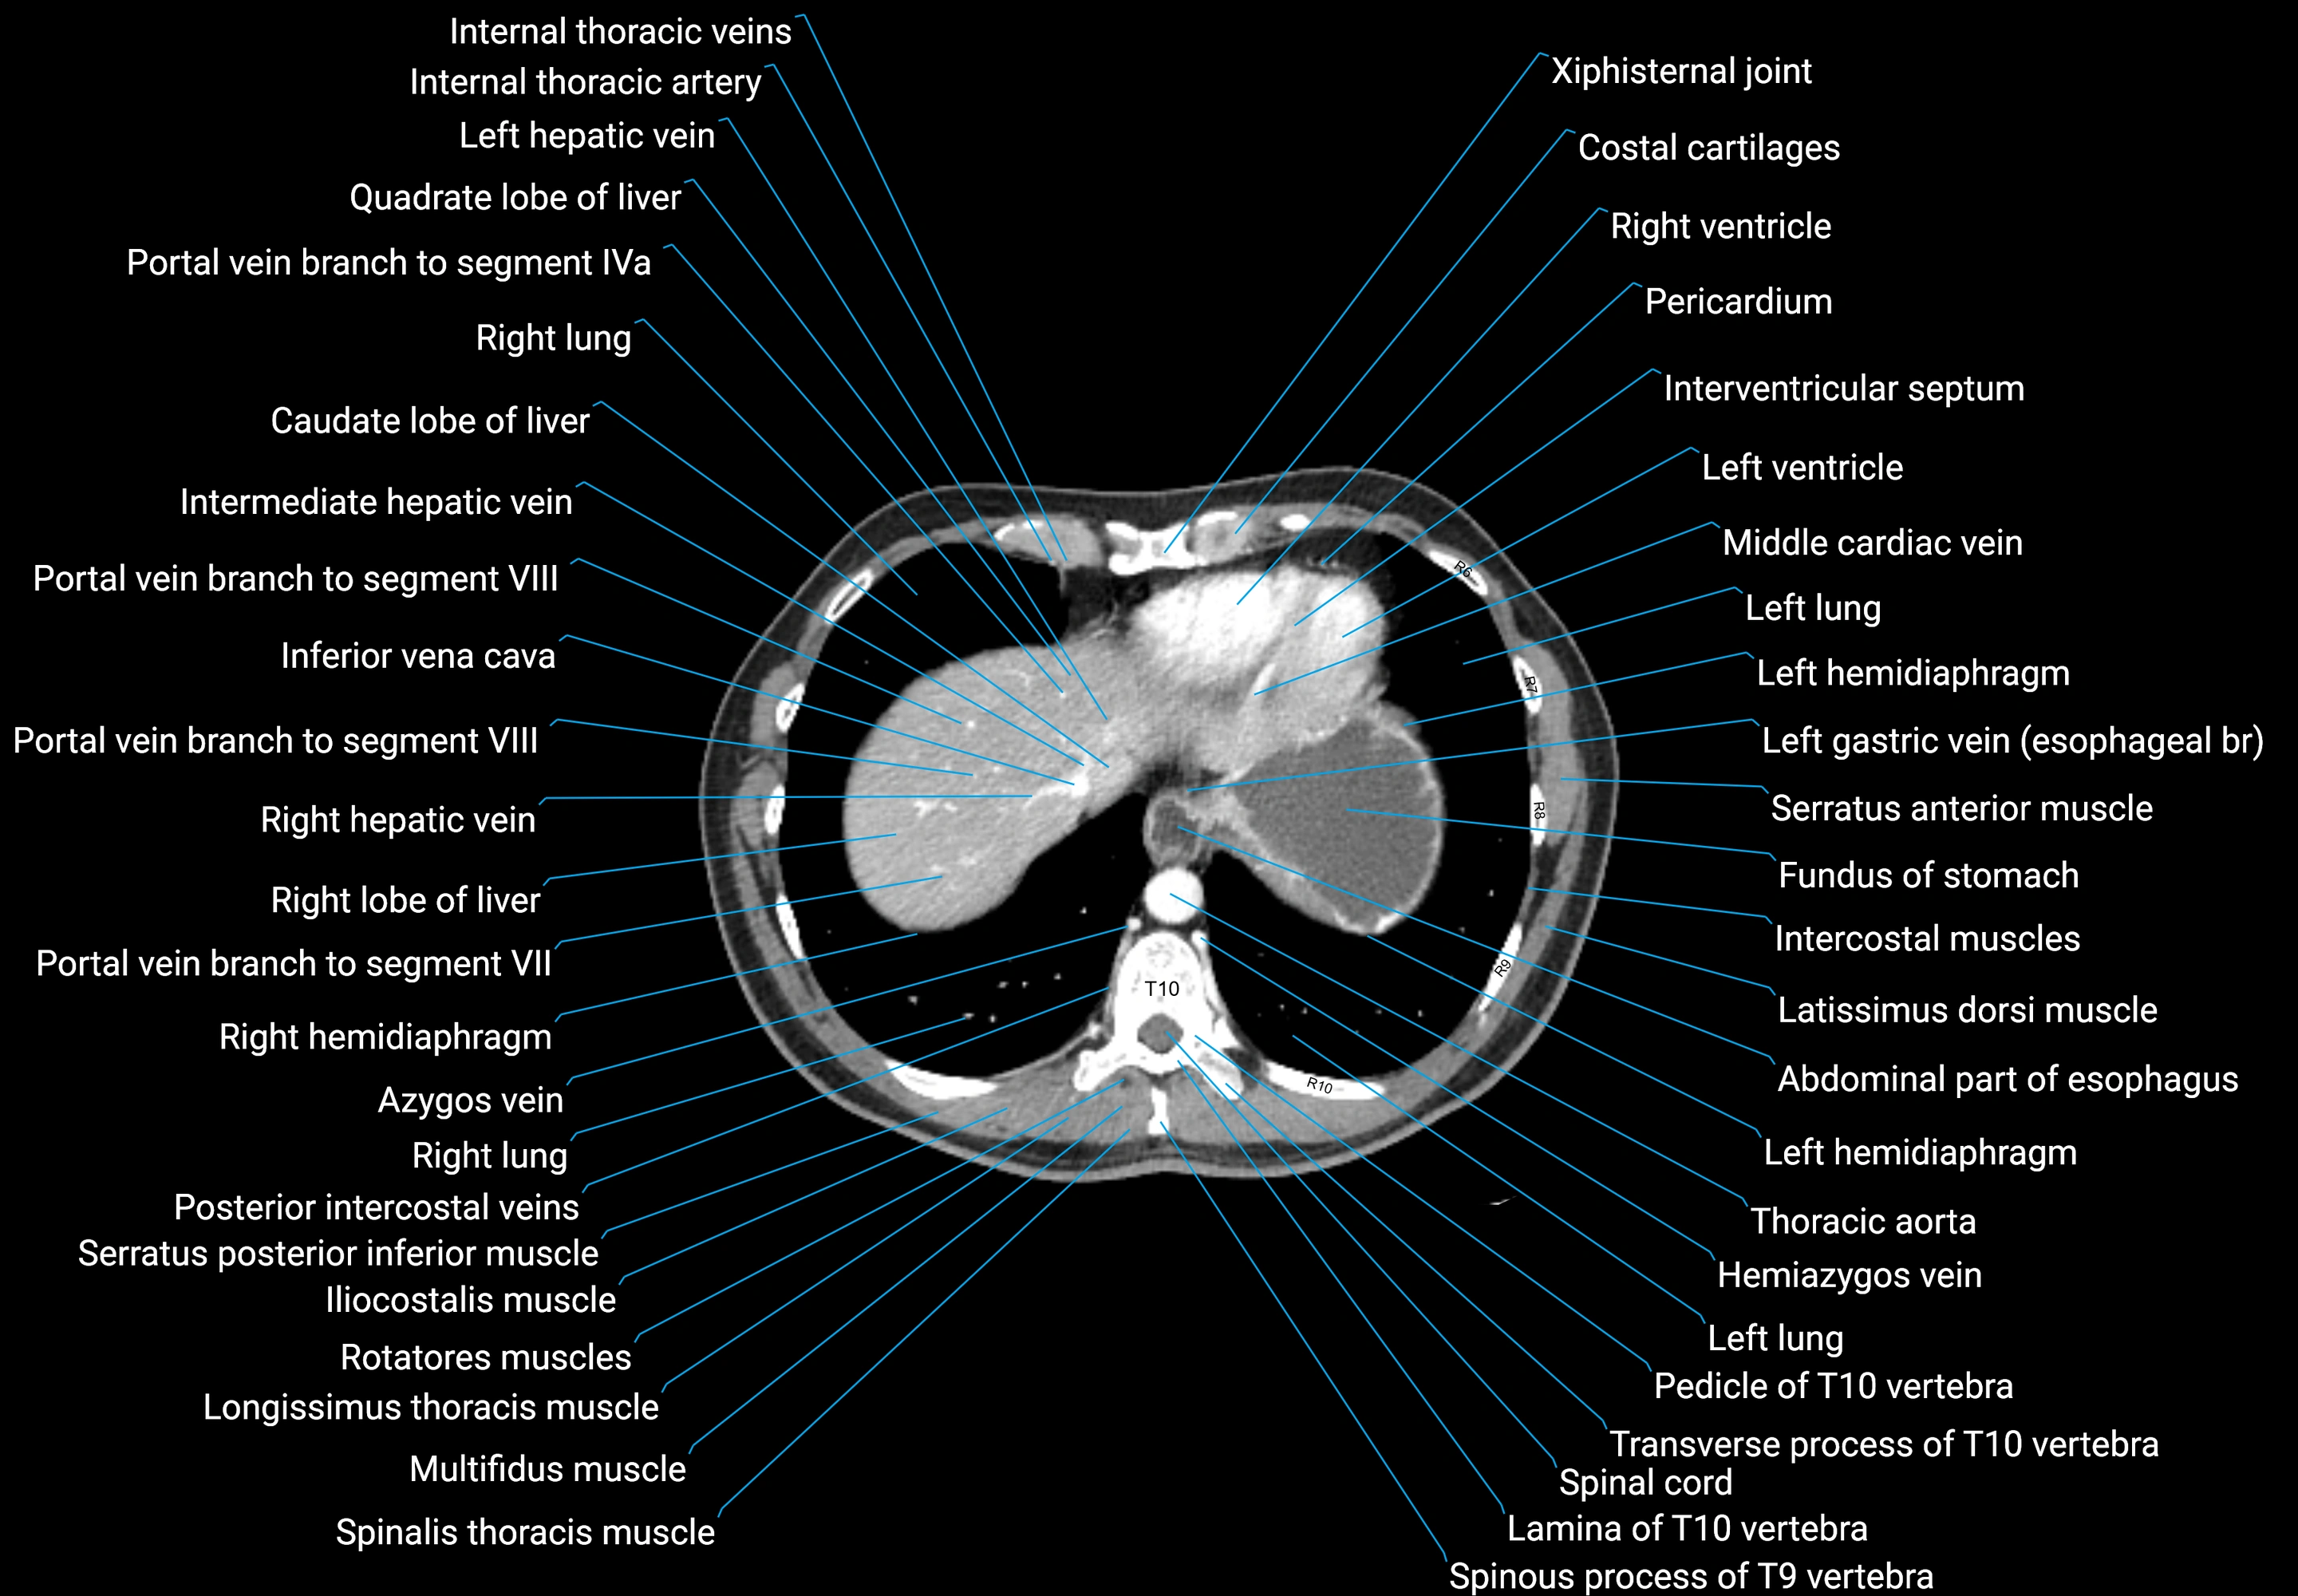

CT images